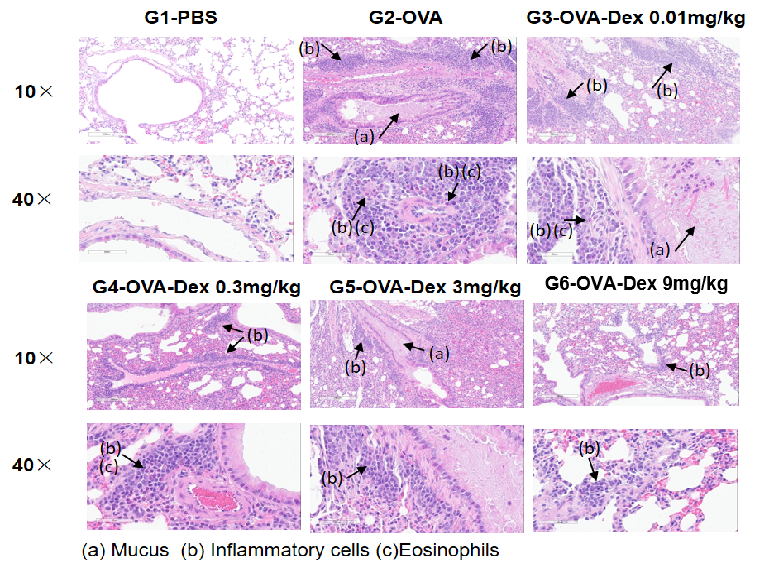

Airway Histology in Asthmatic Mouse Model

H&E staining of lung tissue in OVA-induced asthmatic mice.

Histological analysis revealed no pulmonary inflammation in the G1 control group. In the G2 (OVA-only) group, vascular and peribronchial inflammation and mucus secretion were markedly increased, confirming successful asthma model induction. Dexamethasone treatment (G3) reduced inflammatory cell infiltration and mucus production. These results validate the OVA-induced BALB/c mouse model as a platform for evaluating corticosteroid immunosuppressive efficacy.

ELISA-based detection of serum IgE in OVA-induced asthmatic mice.

Serum levels of OVA-specific IgE (A) and total IgE (B) were measured by ELISA. The G2 (OVA-only) group showed significantly elevated IgE levels compared to the G1 control group, confirming successful asthma induction. Dexamethasone treatment reduced OVA-specific and total IgE levels in a dose-dependent manner, supporting its immunosuppressive efficacy.